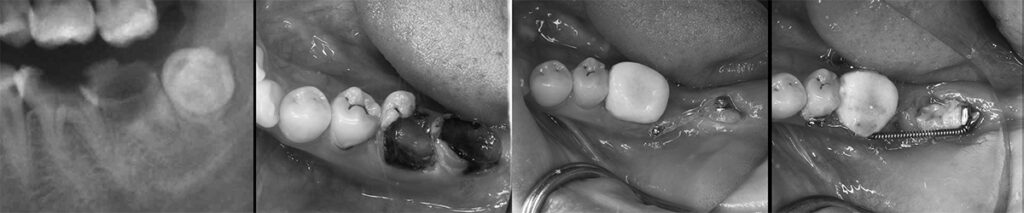

世代が上がれば後方の90度変位した埋伏智歯の移植利用を考えるが歯髄失活は免れないため、困難な矯正であるが萌出間もない大臼歯として今後を託せる生活歯のまま保存する。 矯正用のアンカースクリューと各種装置を智歯に接着させ、移動の各段階で交換しながら抜歯した第二大臼歯部に誘導する。 第一大臼歯は保存治療後ジルコニアセラミック冠で歯冠修復し約7年経過。 治療期間は 2017/12~2019/03

矯正力のかけ方は智歯の萌出状態によって変更

左:治療開始時2017/12 右:健診時2023/07